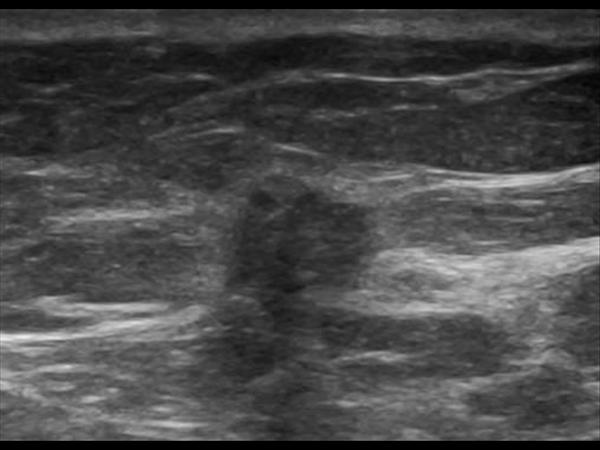

Ung thư vú

Ung thư vú - Ảnh 2

Ung thư vú - Ảnh 3

Ung thư vú - Ảnh 4

Ung thư vú - Ảnh 5

» Thông tin: Nữ giới – 71 tuổi.

» Lâm sàng: Khối tuyến vú.